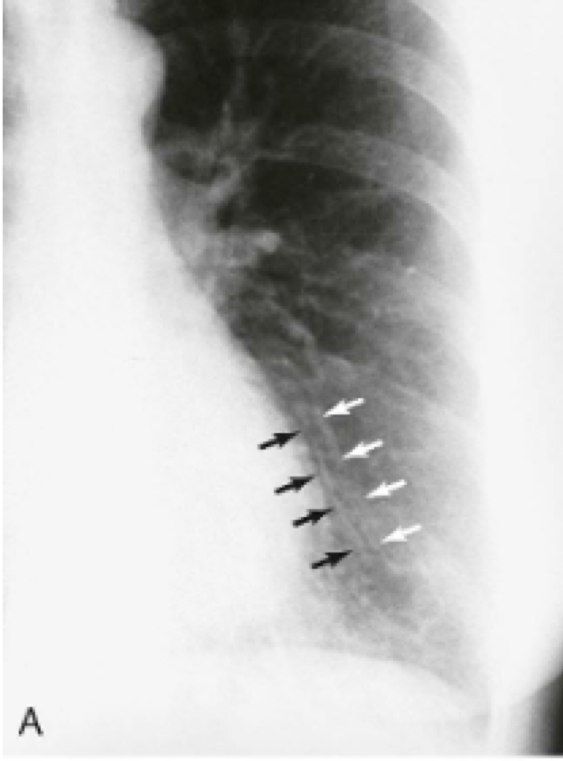

Question 23

Question

In what diseases will you see this?

Answer

• COPD

• CHF

• Tuberculosis

• Pneumothorax